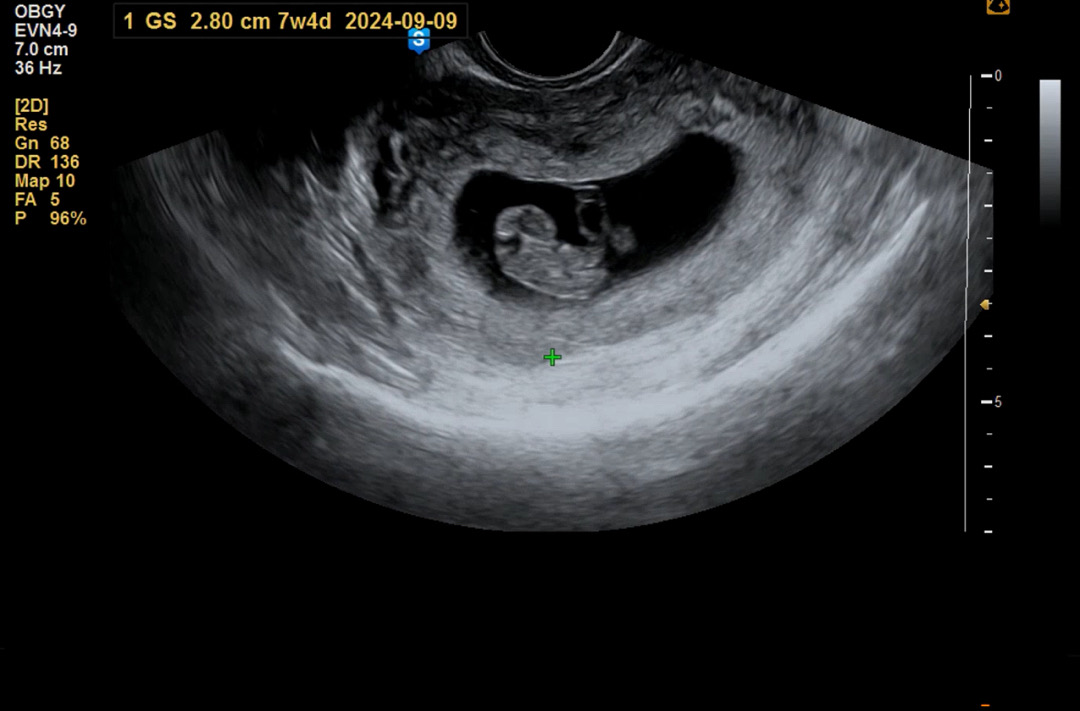

초음파 보고왔었어요!

이때는 8주차때고 지금은 9주차라 이때보다 더 성장했겠죠?! 잘 자라고 있다해서 안심하고 왔어요!! 그나저나 성별이 궁금해서 미치겠네요....!!!!😛❤️ 병원에선 16주 땡~하면 알려쥬시려나요..?